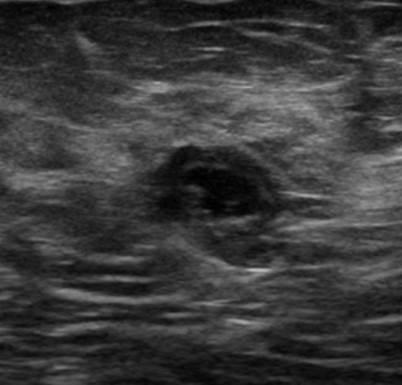

Ung thư vú

Ung thư vú - Ảnh 4

» Thông tin: Nữ giới – 50 tuổi.

» Lâm sàng: Kiểm tra sức khỏe.